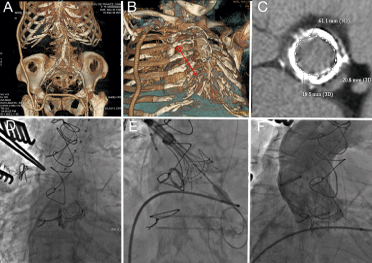

Direct Aortic Evolut R Implantation as Valve-In-Valve in a Patient Affected by Leriche Syndrome

Transcatheter aortic valve implantation (TAVI) has been designed to treat elderly patients with severe aortic stenosis considered high-risk surgical candidates.